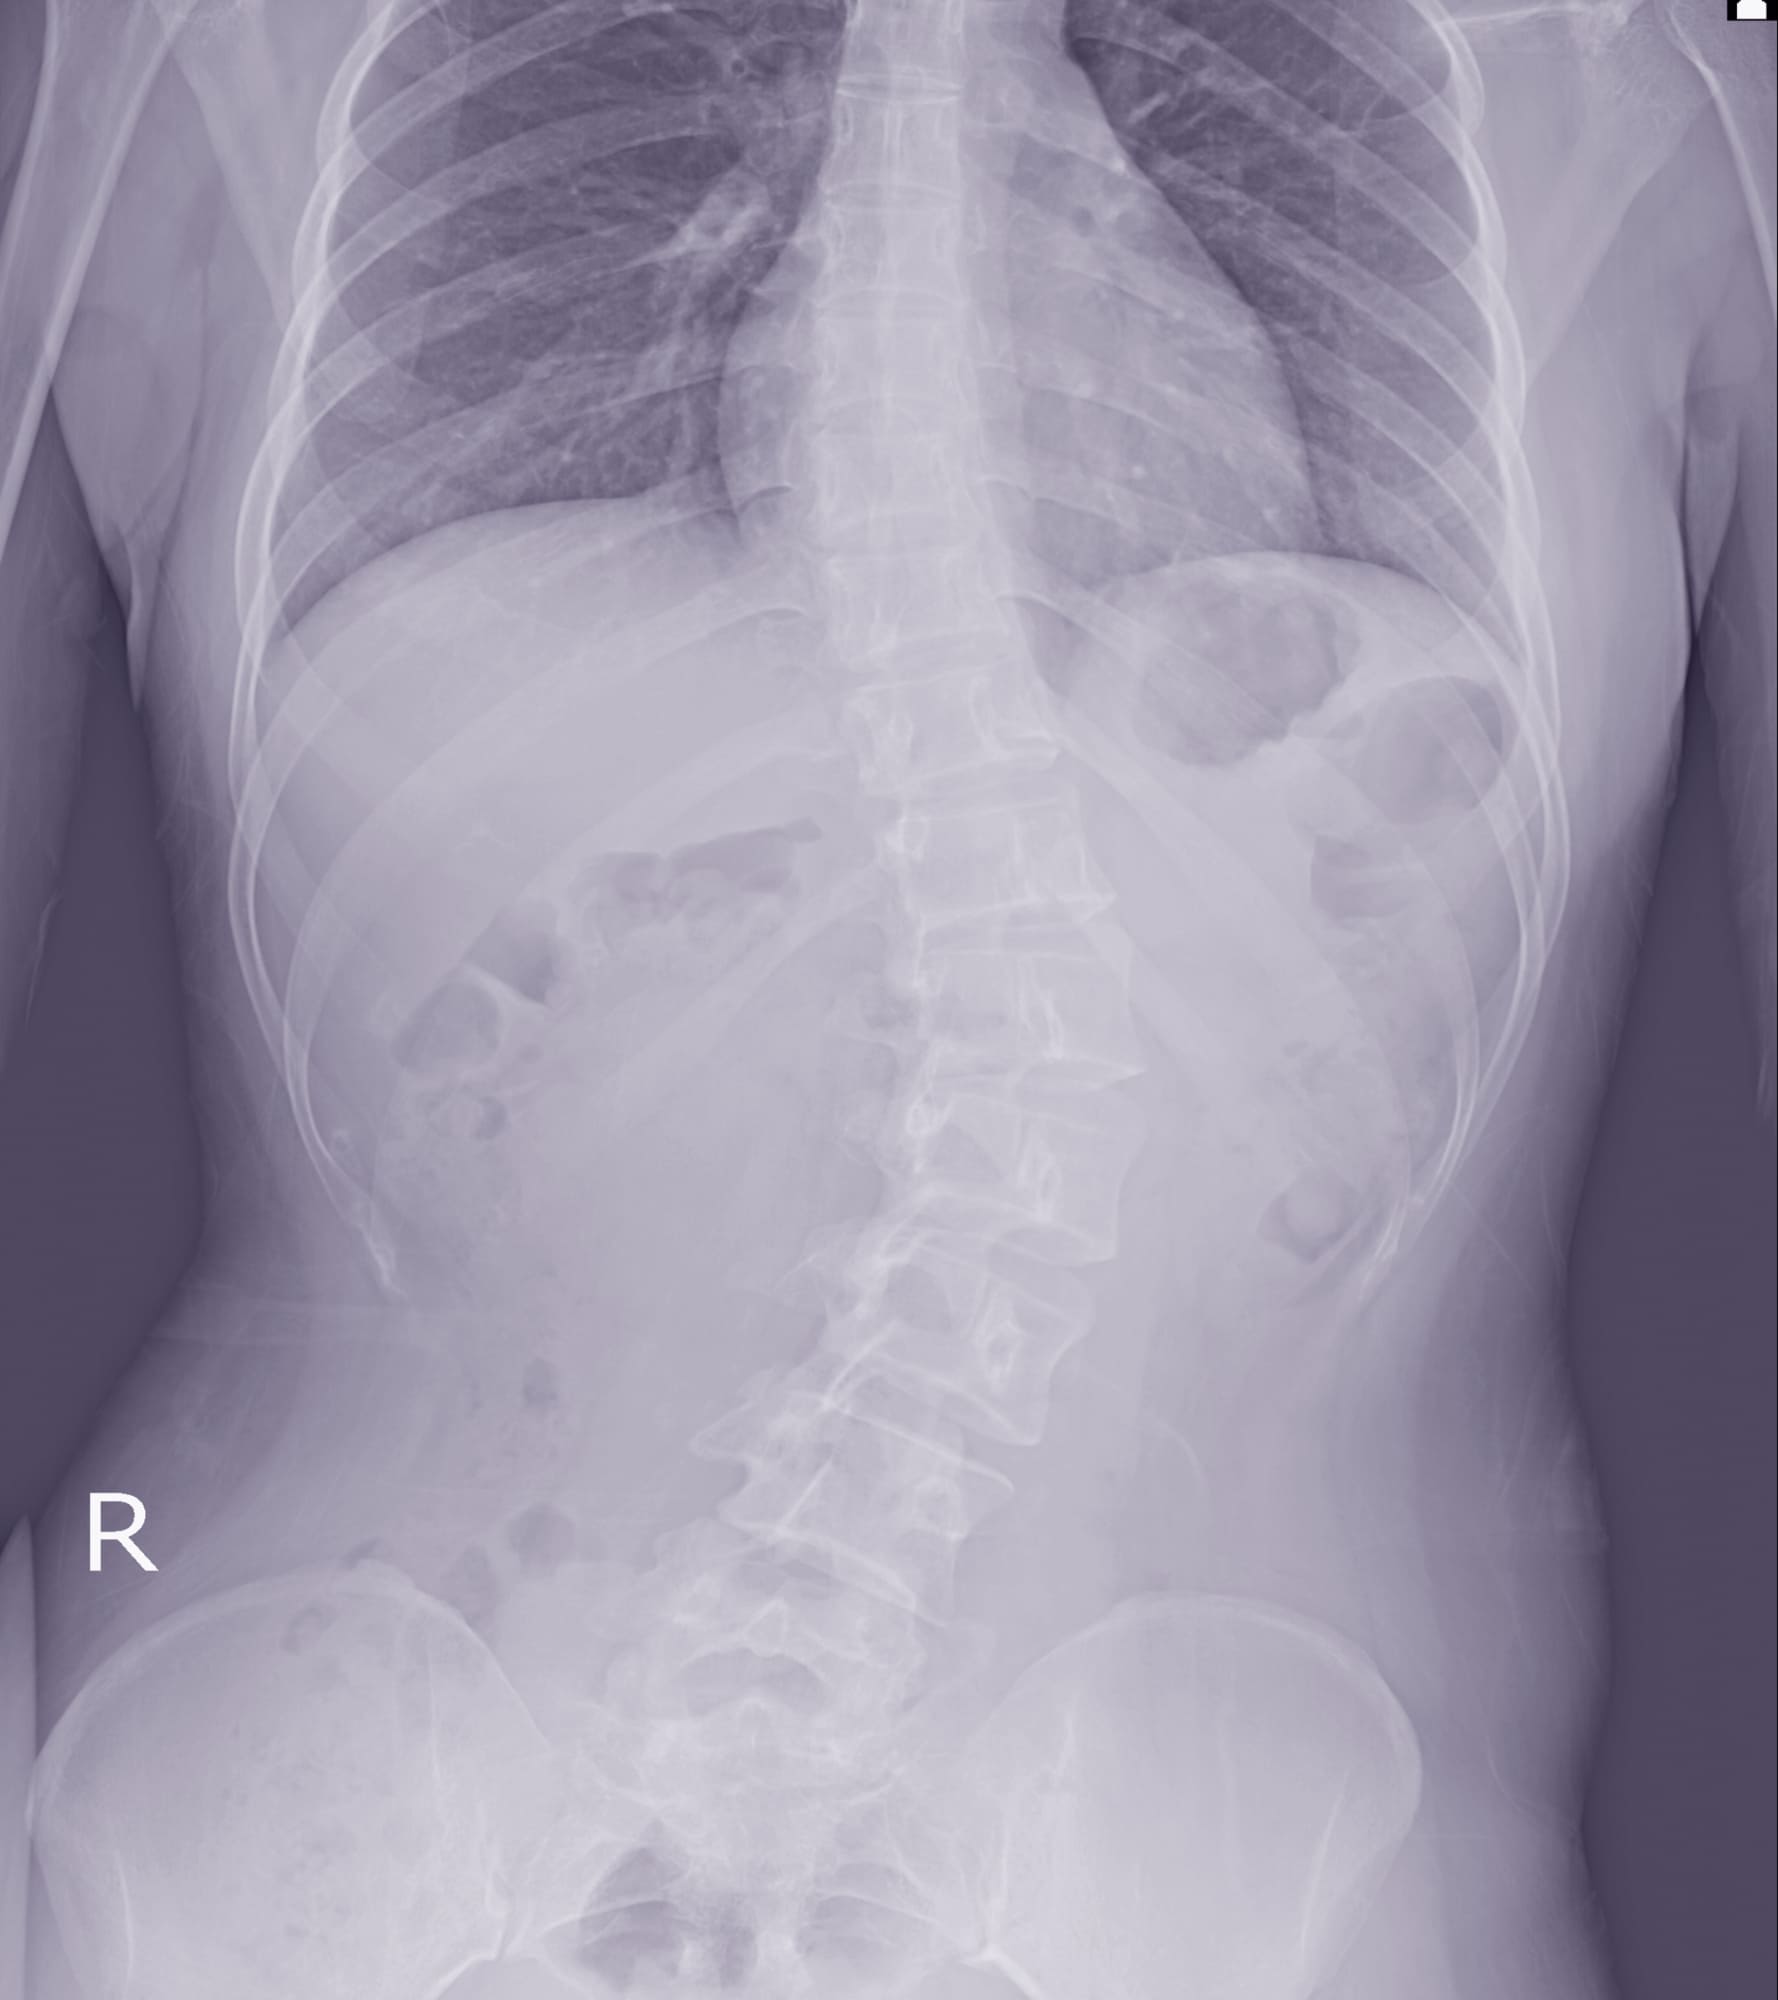

Scoliosis is a musculoskeletal disorder characterized by a sideways curvature of the spine. When viewed from behind, a healthy spine appears straight. However, a spine affected by scoliosis may have an S or C-shaped curve.